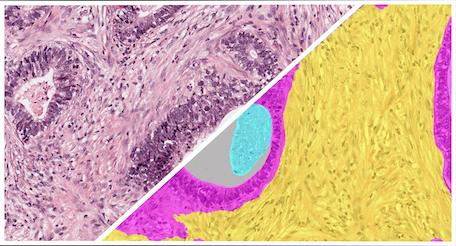

The Breast IHC Tumor Detection App is a pre-trained HALO AI classifier designed to detect, segment, and quantify tumor and other area across hematoxylin and DAB-stained whole-slide digital images of breast cancer.

High levels of variability are often encountered in image analysis but is no match for HALO AI. Common sources of variability include diverse morphologies, alterations of morphologies from staining protocols, differences in tissue quality, uneven staining, and more.

HALO AI can be easily trained to accommodate variability to deliver accurate segmentation and classification results across large studies. HALO AI can even be trained to work across vastly different stains such as PAMS, Trichrome, H&E, and IHC.